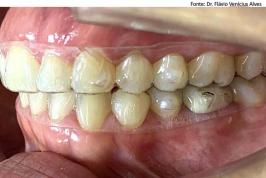

Alinhadores: o protagonismo é do paciente